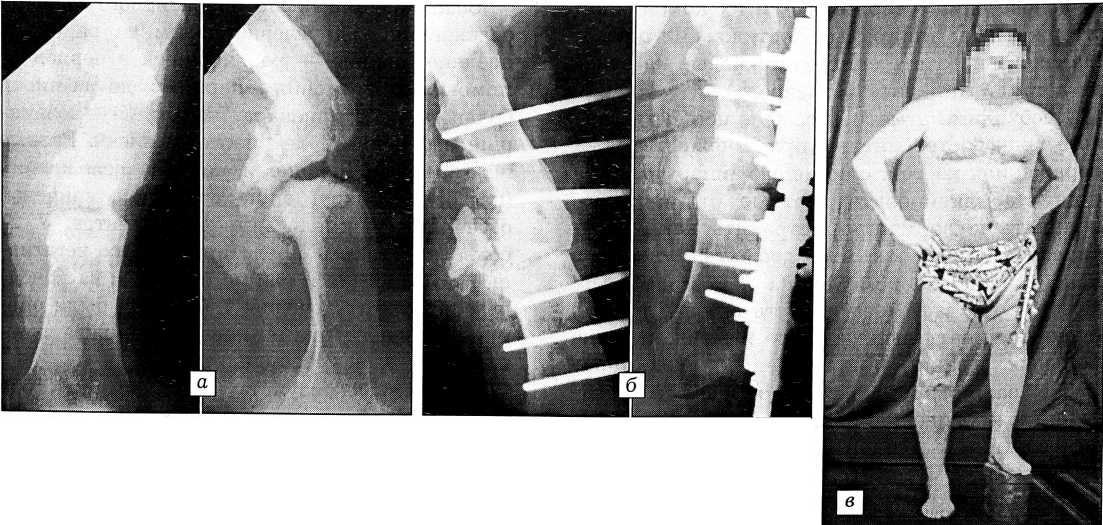

Больной Ш., 49 лет, в октябре 1989 г. в результате автоаварии получил множественную травму — открытый перелом диафиза левого бедра, закрытый перелом шейки левого бедра, открытый перелом костей правой голени, разрыв лонного сочленения, разрыв крестцово-подвздошного сочленения справа. В одной из московских больниц была произведена первичная хирургическая обработка ран, наложено скелетное вытяжение. Через 10 дней выполнен остеосинтез шейки левого бедра трехлопастным гвоздем, перелом диафиза бедра фиксирован пластиной. В послеоперационном периоде развилось нагноение с исходом в остеомиелит. Через 5 мес пластина была удалена и произведена секвестрнекрэктомия, но купировать воспаление не удалось. В результате последующих секвестрнекрэктомий образовался дефект диафиза бедренной кости в 16 см, дважды производился остеосинтез спицестержневым аппаратом. Фиксация, продолжавшаяся 5 и 6 мес, к успеху не привела, добиться сращения не удалось. Аппарат был снят.

При поступлении в ЦИТО 10.07.92: ходит с помощью костылей без опоры на левую ногу. Определяется атрофия мягких тканей левого бедра и левой голени (около 3 см). По наружной поверхности бедра имеются два послеоперационных рубца длиной до 20 см. В средней трети бедра патологическая подвижность в пределах 15°. Свищей нет. После клинико-рентгенологического обследования поставлен диагноз: ложный сустав в средней трети левого бедра с дефектом кости, укорочение левой нижней конечности на 16 см; хронический остеомиелит в стадии ремиссии (рис. 1, а). Перелом шейки бедра сросся.

Произведена операция: удаление трехлопастного гвоздя из проксимального конца левого бедра, резекция зоны ложного сустава с секвестр- некрэктомией, остеосинтез стержневым аппаратом (рис. 1, б, в).

Рис. 1. Больной Ш. Рентгенограммы левого бедра при поступлении (а) и после секвестрнекрэктомии и остеосинеза в стержневом аппарате (б); внешний вид после секвестрнекрэктомии и остеосинтеза (в): укорочение левой нижней конечности на 16 см.